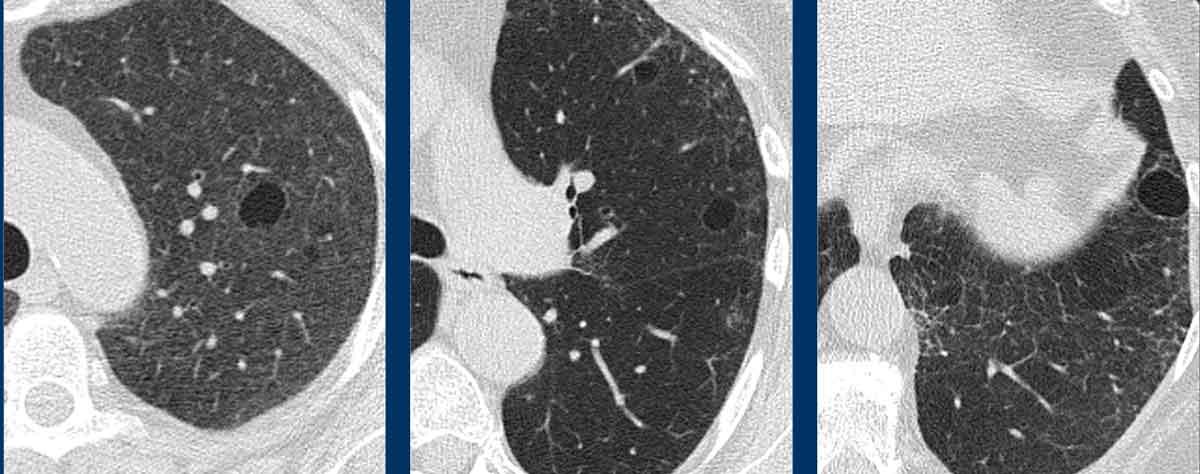

Viêm phổi kẽ dạng bong vảy (DIP) có mối liên quan chặt chẽ với hút thuốc lá.

DIP biểu hiện dưới dạng các nang thành mỏng đối xứng nằm trong vùng kính mờ (ground-glass), ưu thế ở vùng đáy phổi và ngoại vi.

Thường kèm theo các dấu hiệu xơ hóa.

Các hình ảnh này thuộc về một phụ nữ 65 tuổi có triệu chứng khó thở và tiền sử hút thuốc lá.

Hình ảnh tổn thương

Có các nang thành mỏng nằm trong vùng kính mờ kèm theo xơ hóa nhẹ.

Lưu ý hình ảnh giãn phế quản do co kéo (mũi tên).

Tiếp tục xem thêm hình ảnh của bệnh nhân này…

Chẩn đoán phân biệt chính của các nang phổi kết hợp với kính mờ là DIP và LIP (viêm phổi kẽ lymphocytic).

Chẩn đoán có khả năng nhất là DIP, do bệnh nhân có tiền sử hút thuốc lá và các nang chỉ xuất hiện trong vùng kính mờ.

Các nang trong DIP phân bố ở ngoại vi vùng phổi dưới và thường kết hợp với xơ hóa.

DIP cũng có thể có phân bố lan tỏa.

Đây là một ví dụ điển hình.